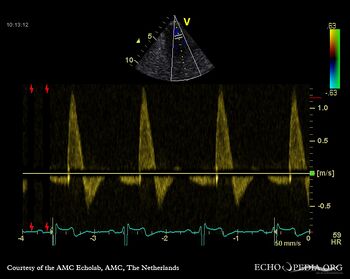

Case 10